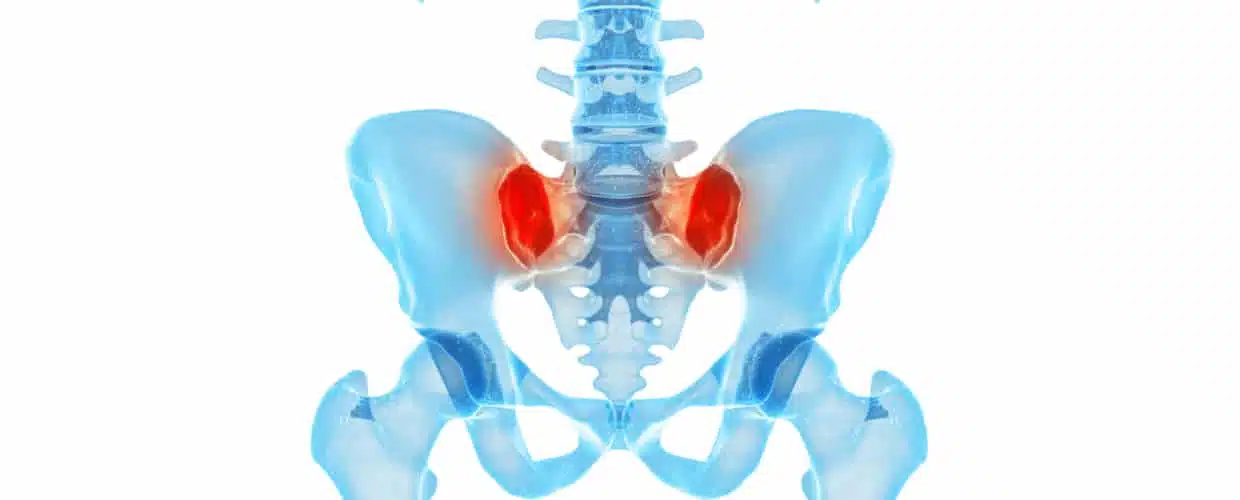

Sacroiliac joint fusion is a minimally invasive surgical procedure designed to stabilise the sacroiliac (SI) joint and reduce chronic pain caused by joint dysfunction. The sacroiliac joint, located at the base of the spine where the sacrum connects to the iliac bones of the pelvis, can become painful due to conditions such as arthritis, injury, or degeneration. This procedure fuses the joint using bone grafts or implants to limit movement and provide long-term relief.